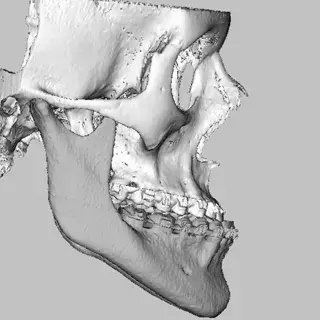

3D Systems' VSP® surgical planning solutions for craniomaxillofacial (CMF) applications received FDA clearance as a service-based approach to personalized surgery over 10 years ago.

3D Systems and Stryker Corporation have partnered to provide surgeons with best-in-class products and services for craniomaxillofacial surgeries. As a leader in personalized healthcare solutions, 3D Systems has planned and delivered devices for more than 140,000 patient-specific cases. The Stryker Craniomaxillofacial business specializes in providing patient-specific options and innovative solutions that help drive efficiencies in surgical suites. The combination of Stryker’s specialized team and advanced implants with 3D Systems' cutting-edge 3D printing technologies and expert consulting services positions both companies to provide a superior level of service to healthcare professionals who use these revolutionary solutions.